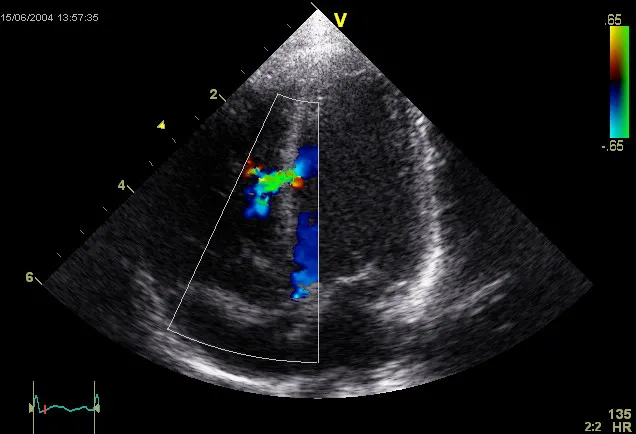

i have a heart condition. this is a reflection i had after a routine checkup

ventricles veins arteries aortas valve and little fibery bits that go

ticking humming and pumping

slowly breaking